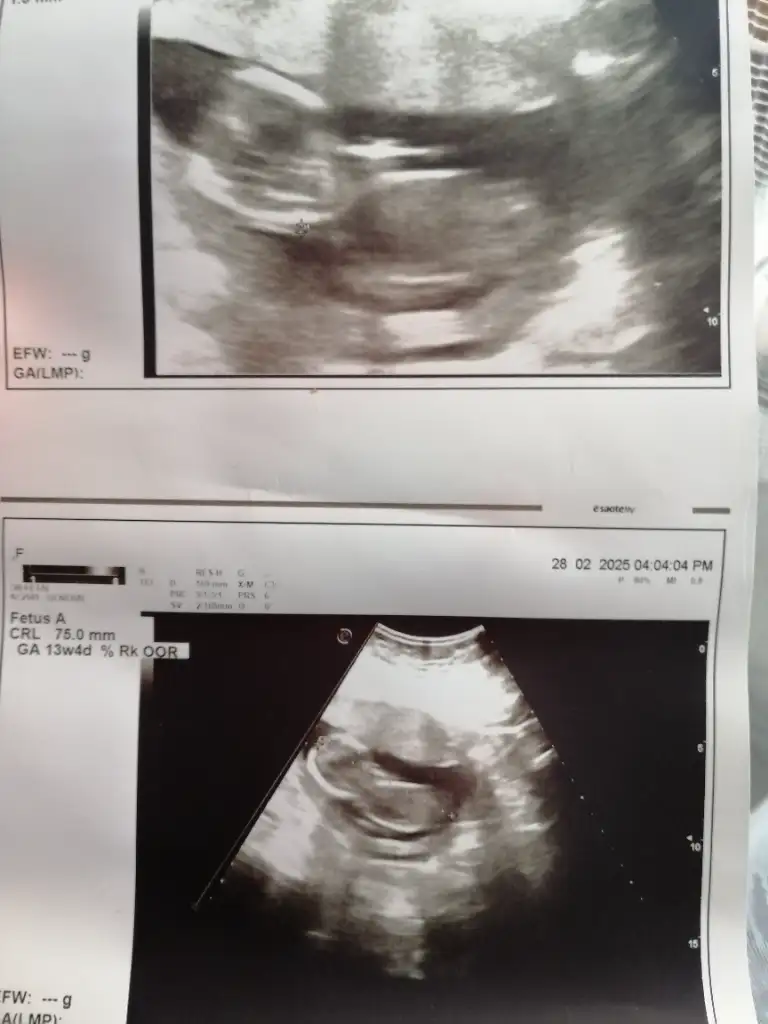

Merhabalar. Lütfen bana bir tahminde bulunur musunuz

Eklentiler

• IMG_20250307_073925.webp

IMG_20250307_073925.webp

22,9 KB · Görüntüleme: 36